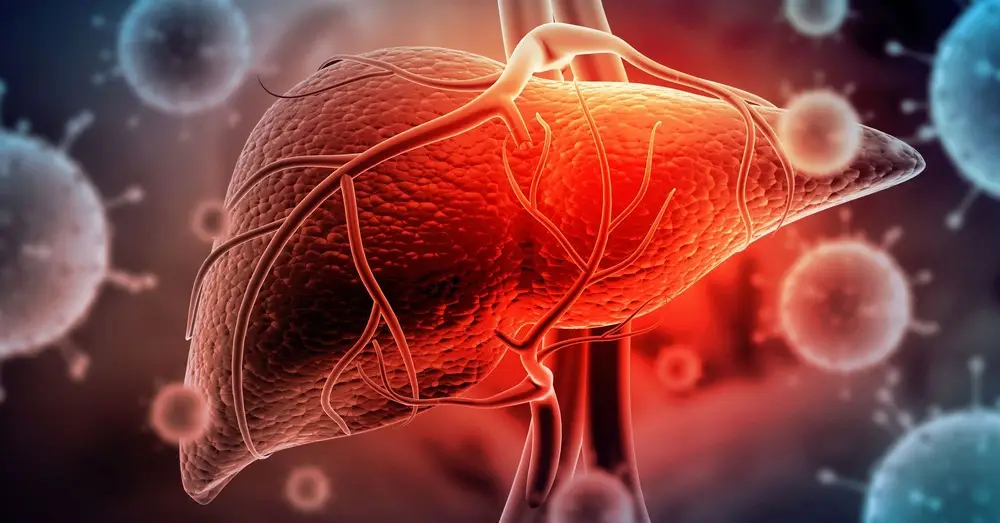

ہیپاٹائٹس بی اور سی کے ساتھ خوف کا تاثر وابستہ ہے۔ اس کا بڑا سبب لوگوں میں پھیلا یہ تاثر ہے کہ یہ مرض لاعلاج اور موت کی گھنٹی ہے۔ ماضی میں یہ تاثر کسی حد تک درست تھا لیکن اب ایسا نہیں۔ ہیپاٹائٹس کے علاج میں نئی پیش رفت کی بدولت اب حالات کافی بدل گئے ہیں۔

٭ ہیپاٹائٹس بی اور سی زیادہ خطرناک ہیں۔ یہ متاثرہ خون لگنے سے پھیلتے ہیں۔